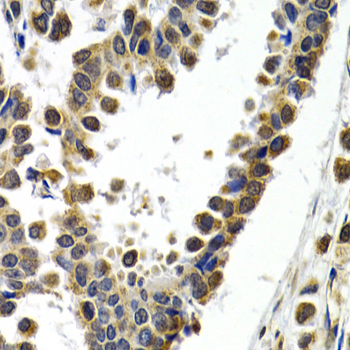

Immunohistochemistry of paraffin-embedded human normal breast using ATF2 antibody at dilution of 1:200 (400x lens).

Immunohistochemistry of paraffin-embedded human breast cancer using ATF2 antibody at dilution of 1:200 (400x lens).